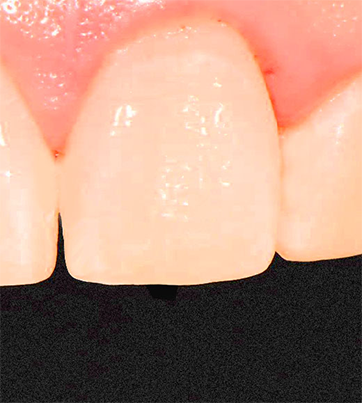

초기 충치 치료의 최선의 선택

레진 치료

치아색과 동일한 재료로 자연스럽게 복원하는 치료법입니다.